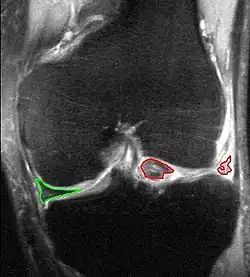

Als Meniskusriss oder Meniskusruptur bezeichnet man einen Riss eines oder beider Menisken des Kniegelenks. Innenmeniskusverletzungen (also des Meniscus medialis) sind wesentlich häufiger als die des Außenmeniskus (Meniscus lateralis). Die Risse werden nach ihrer Verlaufsrichtung in Längsriss, Radiärriss und Schrägriss (Lappenriss) eingeteilt. Bezüglich der Raumebene unterscheidet man Vertikalrisse und Horizontalrisse. Sonderformen sind komplexe Risse, der Korbhenkelriss und ein „flipped meniscus“.[1][2] Eine weitere Sonderform des Meniskusrisses betrifft den anatomisch und therapeutisch besonders zu behandelnden Scheibenmeniskus. Die Diagnose erfolgt durch klinische Untersuchung, Kernspintomographie und Arthroskopie (Gelenkspiegelung). Meniskusrisse sind recht häufig und oft bestehen keine Schmerzen oder Einschränkungen. Nicht jeder Meniskusriss muss behandelt werden.

Vor einer Operation muss die Diagnose meist durch eine MRT bestätigt werden. Dann erfolgt bei älteren Menschen mit geringem sportlichen Anspruch meist eine teilweise Resektion der gerissenen Meniskusanteile mittels Kniegelenks-Arthroskopie (Gelenkspiegelung). Besonders bei Kindern und Jugendlichen haben die Menisken eine zentrale Aufgabe bei der Kniegelenksfunktion und bei deren langfristigem Erhalt. Daher sollten bei Kinder, Jugendlichen und sportaktiven Erwachsenen Meniskusrisse am besten operativ, d. h. arthroskopisch mit einer Naht behandelt werden, um so wenig Meniskusgewebe wie möglich zu opfern.

Meniskusrefixation (Meniskusnaht)

Bei einer Meniskusnaht wird der Riss mit speziellem Nahtmaterial, Nahtsystemen oder Meniskuspfeilen aus resorbierbaren Materialien wieder befestigt. Dies ist allerdings nur bei bestimmten Rissenformen und in durchbluteten Bereichen (rot-rote bzw. rot-weiße Zone) möglich.[5] Bei jüngeren Patienten wird auch bei weniger basisnahen Rissen eine Refixation versucht, um denkbare Folgen einer Meniskusresektion auf das Gelenk möglichst zu vermeiden. Je früher Meniskusrisse operativ versorgt werden, desto größer ist die Aussicht auf eine Ausheilung.[6] Zur Verbesserung der Einheilung wird neben den Nähten eine Anfrischung der Risszone (sogenanntes Needling, also „Nadeln“) durchgeführt, wodurch die Durchblutung lokal verbessert wird. Bei ausgedehnten Rissen mit hoher Bedeutung einer Ausheilung wird zusätzlich die Eröffnung der Spongiosa im Kniegelenk durchgeführt. Dazu wird mit einer arthroskopischen Ahle oberhalb der Notch zwischen den Kondylen eröffnet. Das dadurch austretende stammzellreiche Blut trägt erheblich zur Heilung bei. Das erklärt auch, warum Meniskusnähte aufgrund der Anlage von Bohrkanälen bei einer Kreuzbandplastik eine deutliche besser Heilungstendenz haben. Anschließend muss der genähte Meniskus heilen. Dazu wird die Bewegung des Kniegelenks in der ersten Phase nach der Operation eingeschränkt, wozu eine Schiene zur Bewegungslimitierung getragen wird. Die Belastung kann schnell aufgebaut werden, da der Meniskus dabei nicht belastet wird. Nach etwa drei Wochen kann die Bewegung des Kniegelenks zunehmend freigegeben werden, eine vollständige Aufnahme der sportlichen Tätigkeit erst nach einem halben Jahr, bei gutem Verlauf der Heilung eventuell auch früher. „Sanfte“ sportliche Tätigkeiten, wie zum Beispiel Krafttraining, Radfahren oder Schwimmen können nach circa zwei Monaten aufgenommen werden. Ein Erhalt des Meniskus mittels Naht ist die erfolgreichste Behandlung mit der besten Perspektive für das Kniegelenk.